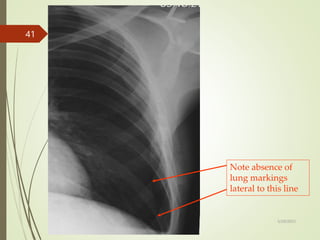

Note absence of

lung markings

lateral to this line